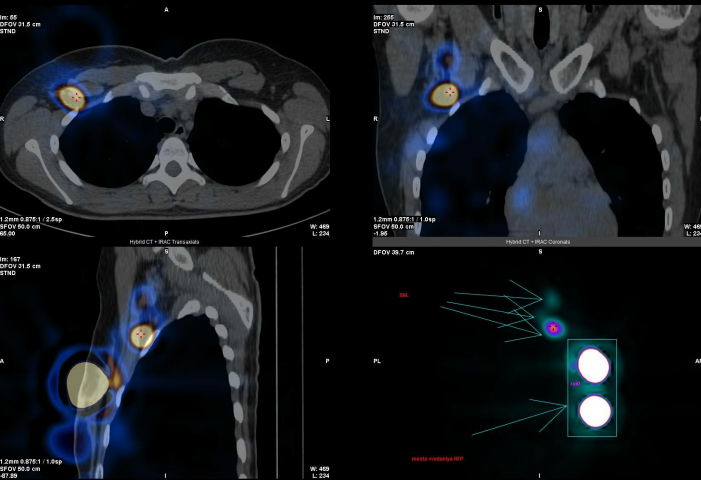

Как же найти те самые сторожевые лимфоузлы? Перед операцией в зону расположения опухоли вводится специальный раствор радиофармпрепарата, который избирательно накапливается в лимфоузлах. Через некоторое время (15-60 минут или немного больше, в зависимости от препарата), выполняется специальная компьютерная томография (ОФЭТ-КТ), по результатам которой в 3D-режиме специалисты получают информацию о сторожевых лимфоузлах.

Лимфоузлы визуализируются в виде ярких точек.

Визуализация сторожевых лимфоузлов